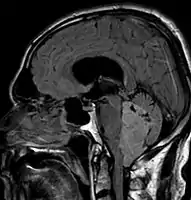

- Ependymoma of 4.ventricle in MRI.